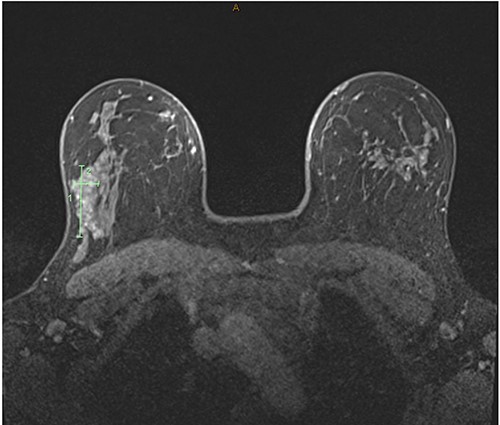

A gravida 1 para 0 (G1P0) premenopausal 31-year-old female presented with new asymmetrical firmness in the right upper outer breast. She had a history of a bilateral wise pattern breast reduction, took no regular medications and was a nonsmoker. She had a maternal family history of ovarian cancer diagnosed in fifth decade of life. Bilateral breast examination revealed no overlying skin or nipple changes, and a discrete mobile firmness in the right upper outer breast, and no palpable lymphadenopathy. The ultrasound demonstrated increased density and a glandular ridge at 9 O’clock 6 cm from the nipple of the right breast, breast imaging-reporting and data system (BI-RADS) classification score of 3 (Fig. 1A). Mammography demonstrated normal breast tissue (Fig. 1B). Core biopsy was indicative of benign breast tissue with a differential of a breast hamartoma. The patient proceeded to undergo magnetic resonance imaging for further characterization, which showed asymmetric fibrocystic change and nodular glandular tissue with enhancement across a large span (15 mm × 45 mm × 28 mm) on the right lateral breast without a focal lesion (Fig. 2). Breast malignancy could not be excluded, thus the patient proceeded to a diagnostic excisional biopsy. Histopathology revealed a 52 mm span of gynaecomastia-like change of the female breast, with a tri-layered pattern of ductal hyperplasia focally, as has previously been described in male gynaecomastia (Fig. 3) [1]. An underlying aetiology was not found on postoperative serological investigations, and the patient continued with routine breast screening as per local guidelines.

T1-weighted magnetic resonance images of the bilateral breast demonstrating asymmetric fibrocystic change and nodular glandular tissue with enhancement affecting tissue span of 15 mm × 45 mm × 28 mm on the right lateral breast without a focal lesion.